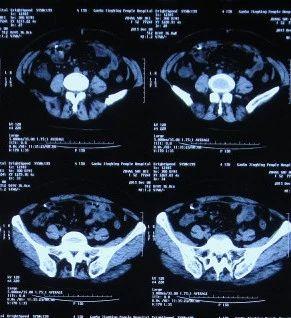

出院后1年零4个月即2015年12月8日(脑室腹腔分流术后1年零5个月),又因“肠梗阻(不全性)”,第2次住入之前手术的医院,当天查腹部CT:仍然有积液(图-6)。给予静脉抗感染、灌肠通便等对症支持,治疗2周后,肠梗阻症状改善后出院。

图-6:2015年12月8日腹部CT

住院次日即2016年8月17日,查腹部CT:仍有腹腔积液(图-8)。

图-8:2016年8月17日腹部CT